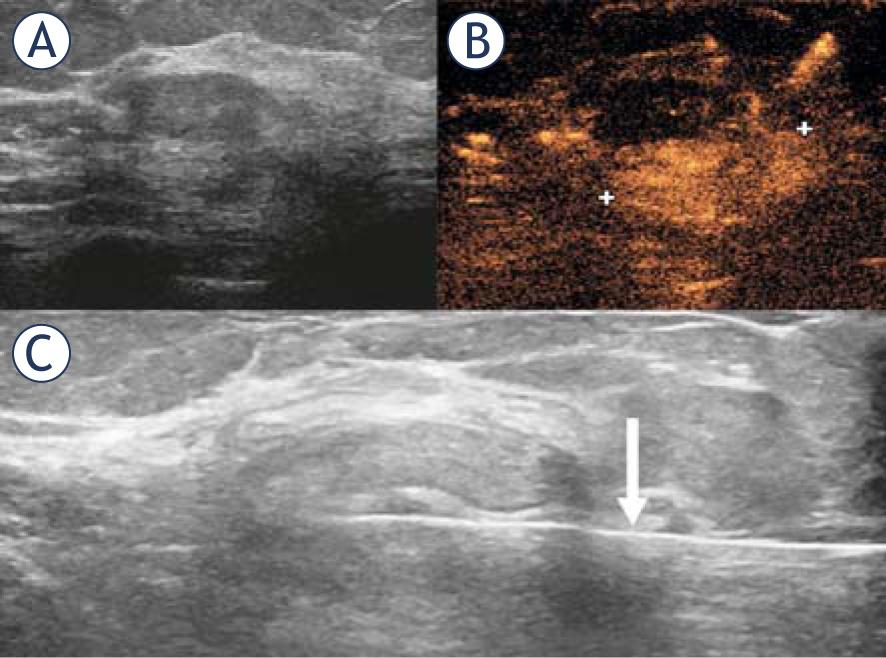

| 1 | 71 | Preoperative local staging | Mass, round, circumscribed, washout kinetic curve | 6 mm | Positive | CEUS-guided CB | CB: Low grade DCIS Final: Low grade DCIS. 3 mm |

| 4 | 54 | Preoperative local staging | Mass, round, circumscribed, heterogeneous, washout kinetic curve | 7 mm | Positive | CEUS-guided clip placement | Final: Intermediate grade IC NST. 5 mm |

| 6 | 66 | Problem solving | Mass, round, circumscribed, ring like enhancement, persistent kinetic curve | 5 mm | Positive | CEUS-guided CB. Follow-up | CB: Fibrocystic lesion, liponecrosis |

| 8 | 61 | Preoperative local staging | Mass, oval, irregular, washout kinetic curve | 10 mm | Positive | CEUS-guided CB | CB: Low grade DCIS Final: low grade IC NST 6 mm and Low grade DCIS 5mm |

| 9 | 53 | Preoperative local staging | Mass, oval, irregular, washout kinetic curve | 16 mm | Positive | CEUS-guided CB | CB: High grade IC NST Final: High grade IC NST. 13 mm |